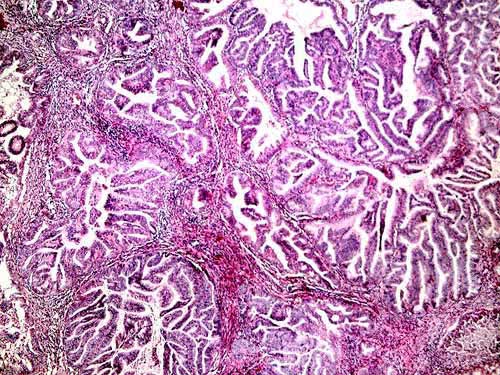

Endometrial Biiopsy in a 55 year old woman with uterine bleeding for 2 weeks (20x - 400x)